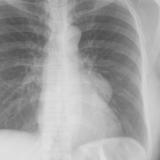

Case 4b

Peric effusion

Date: 03/17/2004

Views: 2441